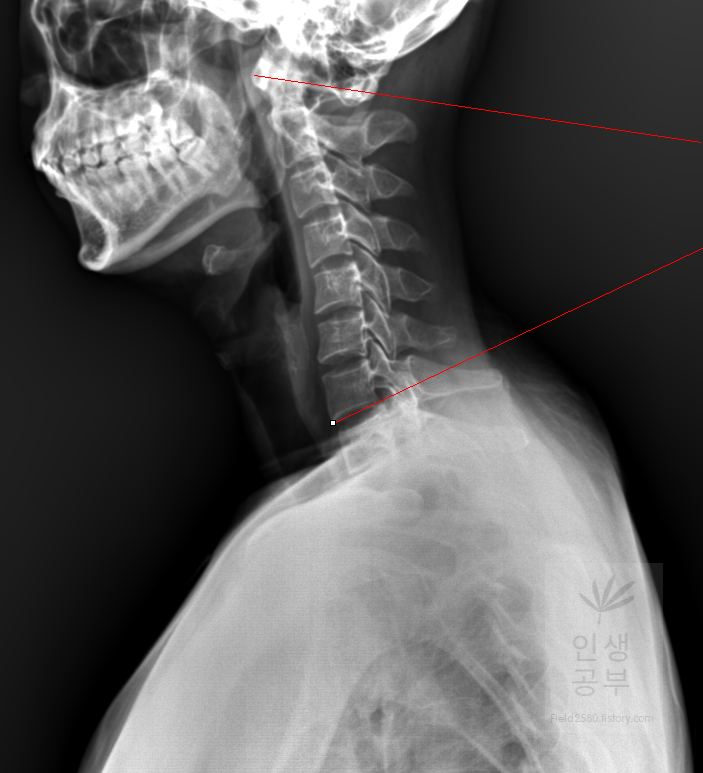

일곱번째 목뼈 추체 밑면(Inferior endplate of C7)과 평행한 선을 그어줍니다.

위쪽에 있는 선은 첫 번째 목뼈(C1) 선을 그리기 위해 제일 튀어나온 앞쪽 부분 가운데 지점에(Center of Anterior arch)에서 시작해서 후궁(Posterior arch) 제일 좁은 부위 가운데를 지나는 선이 되도록 이동해줍니다. 선 이름을 고리 뼈 선(APL : Atlas Plane Line)이라고 합니다. 점은 조금 더 정확하기 위해서 하는 것이 찍어도 되고, 점을 찍지 않은 상태에서 선을 그으셔도 무방합니다. 아래쪽에 있는 선은 일곱번째 목뼈 추체 밑면(Inferior endplate of C7)과 평행하게 선을 맞춰줍니다. 노란색 글자와 숫자가 아래줄 맞춰 준 곳에 있는데 A는 Angle 각도이고 옆에 있는 숫자가 Cobb 각입니다.